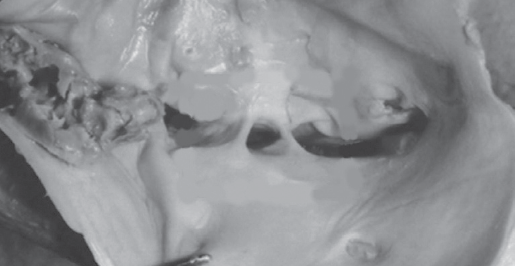

Сдавление левой общей подвздошной вены между правой общей подвздошной артерией и 5-м поясничным позвонком и фиброзные спайки в ней впервые были описаны немецким патологом R. Virchow в 1851 г. [1]. R. Virchow отмечал, что глубокие илеофеморальные тромбозы встречались слева в 5 раз чаще, чем справа. Фиброзные спайки (шварты) в компрессированной подвздошной вене являются неизбежным патогенетическим звеном этого заболевания (рис. 1).

Рис. 1. Шварты (синехии, спайки) в просвете левой общей подвздошной вены по H. Mitsuoka et al. (2013)

Fig. 1. Synechiae (adhesions) in the lumen of the left common iliac vein according to H. Mitsuoka et al. (2013)